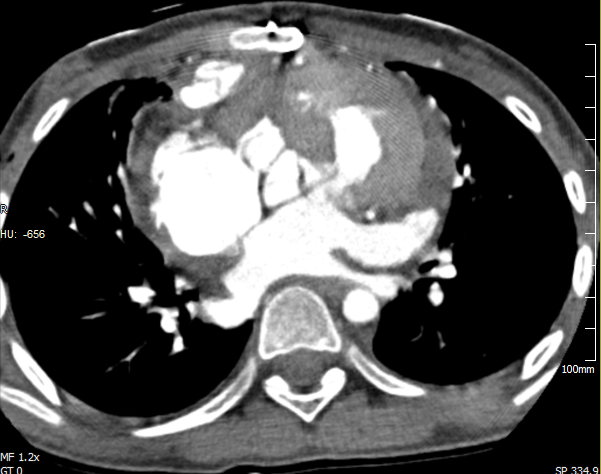

术后CT显示新建的右室第二通道通畅

患者,女性,10岁。自出生后表现为全身青紫,活动耐力下降,虽在多家医院就诊,但均未给予有效的治疗。入院后检测得知其动脉血氧饱和度为60%,属重度缺氧,由于长期严重缺氧,患儿生长发育已受影响。经CTA、超声等多种检查后,确诊为复杂先天性心脏病:矫正性大动脉转位,房间隔缺损,室间隔膜部瘤,功能右室(解剖左室)流出道重度狭窄,三尖瓣返流中—重度。针对本例复杂的右室流出道狭窄问题,吴向阳主任医师团队在术前制定了第一手术方案及备用方案,术中首先采用第一方案疏通右室流出道,并同期矫治其它心内畸形,心脏恢复跳动后测右室压仍很高,证明狭窄未能很好的解除,遂应用备用的“双通道技术”重建右室流出道,心脏再次复跳后测量右室压下降满意。患儿术后恢复顺利,氧饱和度提高至96%,复查超声及CT提示心内畸形矫治满意。